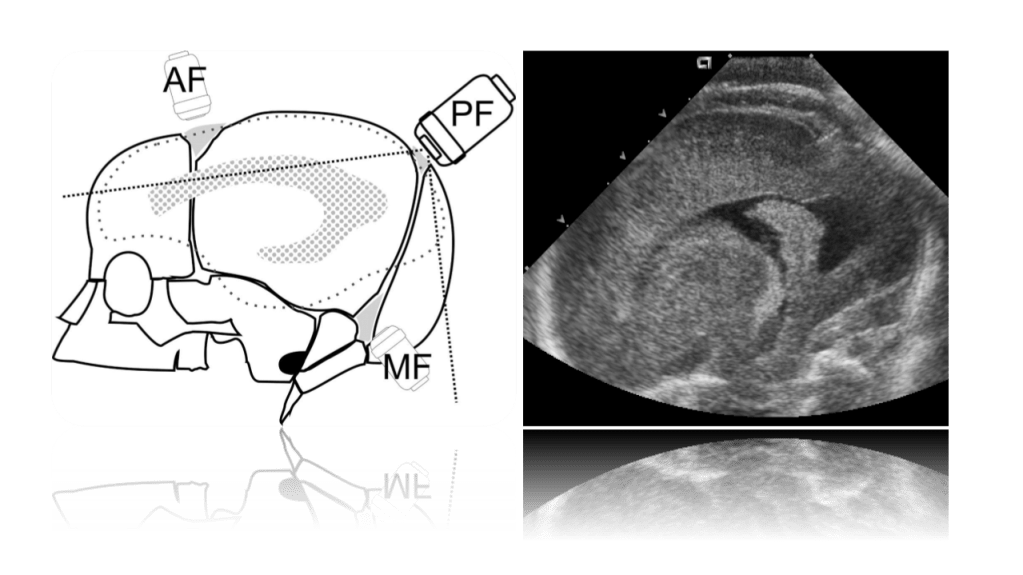

We use primarily the anterior fontanelle using a coronal, sagittal and parasagittal views. Also we scan through the mastoid fontanelle (for the posterior fossa and cerebellar views) and posterior fontanelle (for posterior structures especially the occipital horn to detect dependent hemorrhage) and temporal views for further evaluation.

Posterior Fontanelle